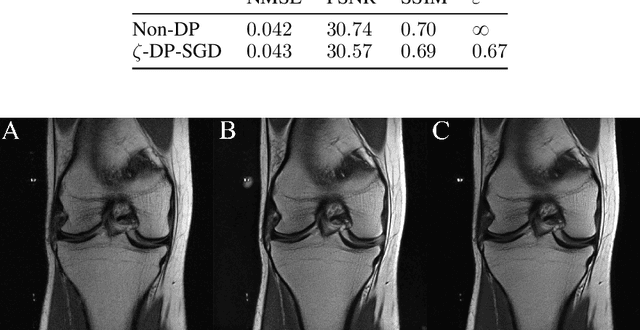

Abstract:We present $\zeta$-DP, an extension of differential privacy (DP) to complex-valued functions. After introducing the complex Gaussian mechanism, whose properties we characterise in terms of $(\varepsilon, \delta)$-DP and R\'enyi-DP, we present $\zeta$-DP stochastic gradient descent ($\zeta$-DP-SGD), a variant of DP-SGD for training complex-valued neural networks. We experimentally evaluate $\zeta$-DP-SGD on three complex-valued tasks, i.e. electrocardiogram classification, speech classification and magnetic resonance imaging (MRI) reconstruction. Moreover, we provide $\zeta$-DP-SGD benchmarks for a large variety of complex-valued activation functions and on a complex-valued variant of the MNIST dataset. Our experiments demonstrate that DP training of complex-valued neural networks is possible with rigorous privacy guarantees and excellent utility.